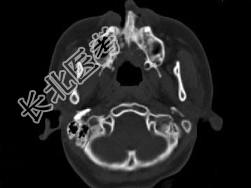

- 单项选择题男,14岁, 脓涕,头痛, CT检查如图,最可能的诊断是 ( )

A、右上颌窦炎

B、腭裂,右上颌窦炎

C、颅面骨发育不良

D、上颌骨骨结核合并瘘道形成

E、上颌骨骨脓肿并瘘道形成